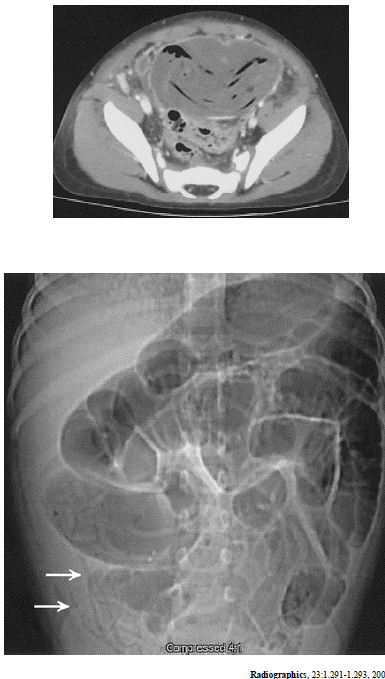

As imagens acima são de um mesmo paciente. Considerando essa imagens e os achados por elas revelados, julgue os itens subseqüentes.

O músculo ilíaco direito apresenta aspecto normal, sem evidências de abscesso.

Existe grande dilatação do cólon sigmóide.

As setas indicam a presença de parasitas.

Há um grande abscesso pélvico.